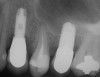

A 55-year-old male was referred for implant placement and prosthetic rehabilitation in the area of tooth No. 15. The tooth had been extracted 4 years prior. The radiograph revealed inadequate bone height for implant positioning (Figure 6). It was decided to insert an implant that was 11.5 mm in length and 3.75 mm in diameter, performing a slight osteotomic maxillary sinus lift. A heterologous bone graft also was planned to obtain a larger sinus lift.

A full-thickness mucoperiosteal flap was raised, and alternating osteotomes were used to prepare the implant site. After achieving a length of 7 mm (Figure 7A and Figure 7B), heterologous bone graft was implanted and the osteotome sequence was repeated. The implant showed primary stability.

Second-stage surgery was performed after 4 months (Figure 8); healing abutments were placed and the soft tissue was allowed to heal for 5 more weeks. Then, splinted porcelain-fused-metal (PFM) crowns supported by custom gold abutments were delivered (Figure 9 and Figure 10).

Figure 6 Preoperative radiograph of the area around tooth No. 15.

Figure 8 At 4 months after treatment, the radiograph revealed the presence of a bone layer surrounding the implant.